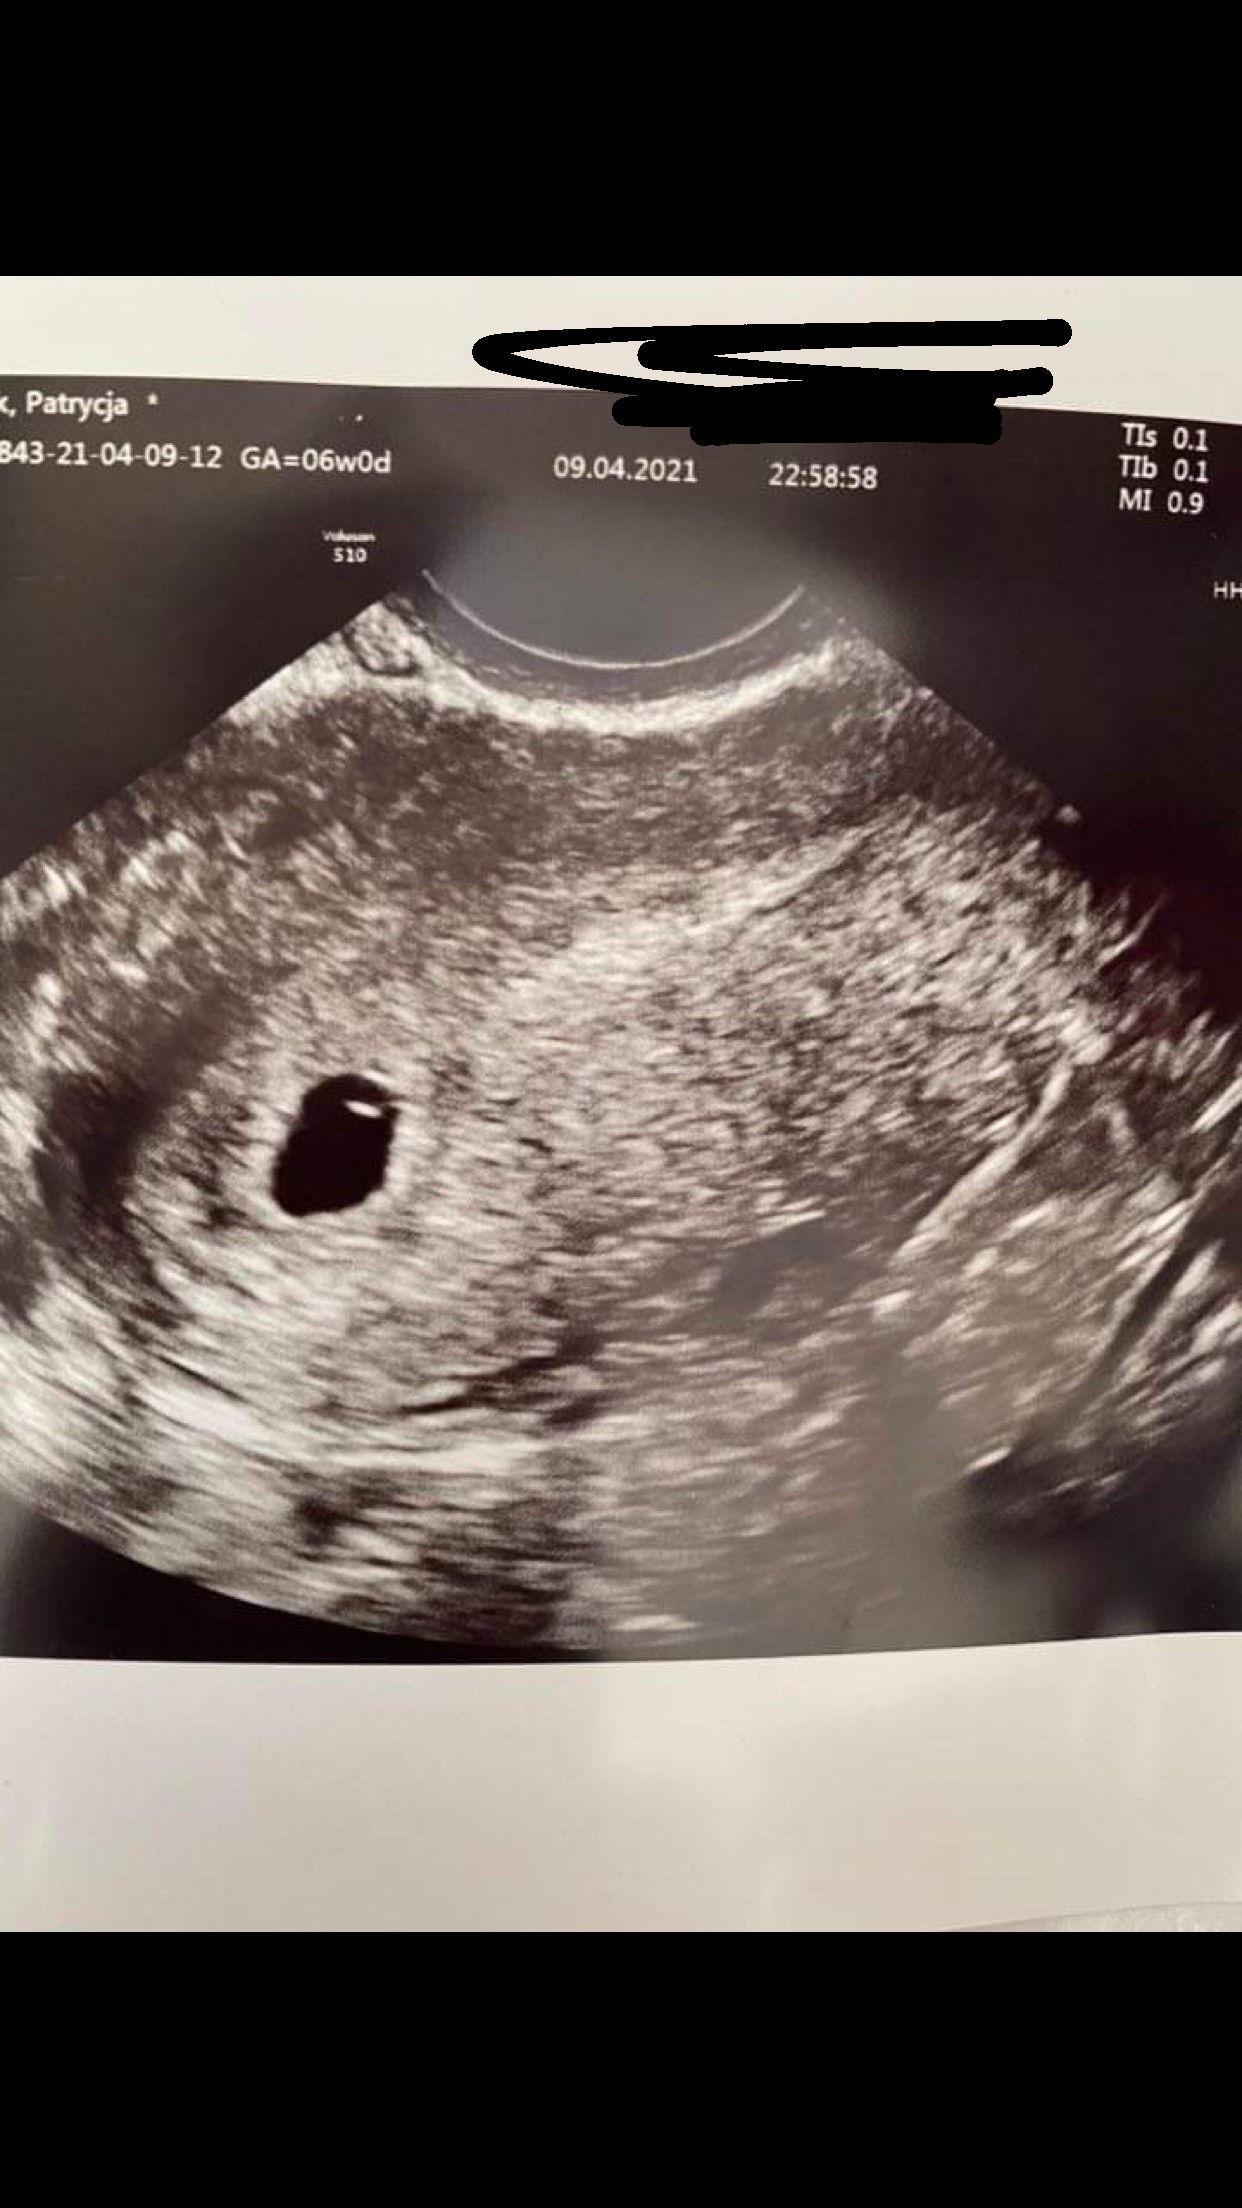

u mnie teraz 6+1widzę 5 tydzień, a dokładnie który tydzień i dzień?

4+6. Wizyta była tak wcześnie bo zależało mi żeby chodzić konkretnie do tego lekarza, a to był jedyny wolny termin. 5.05 idę znów, choć chcialabym o tydzień przyspieszyć, może się udaJeszcze dwie sprawy babeczki! [emoji3590]

1) Pokażcie swoje pierwsze USG i dajcie znać który tydz i dzień ciążyChce się nacieszyć Waszym szczęściem [emoji3590]